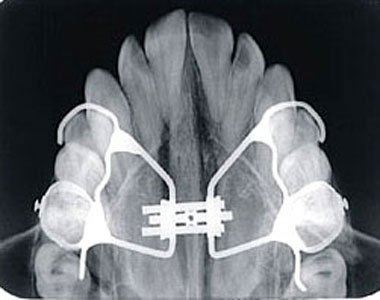

Oclusal